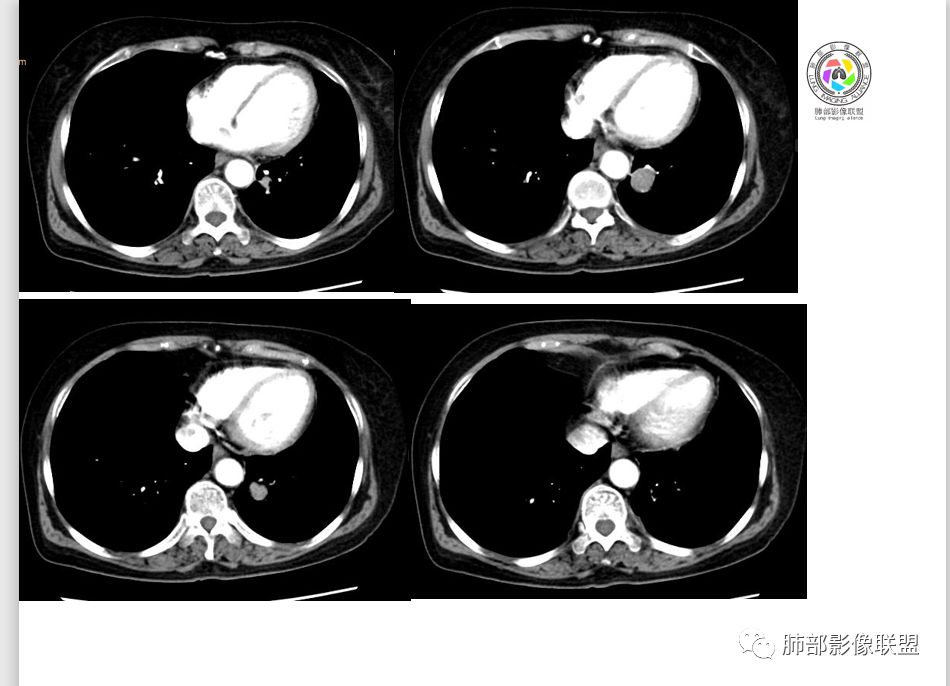

M-Imaging :周围有黑边,错构呢?南边:如果明确没堵塞就好办这个最主要的就是这个支气管是否堵塞没堵塞,支持PSP杨泽锋:如果是气管腔内起源的那就要考虑类癌M-Imaging :不见明显冰山征,没有钙化南边:心里不是很踏实,就是没看到支气管全景Forever:强化如果不高 我还是考虑小细胞肺癌或者腺癌

崔刚:有个层面支气管在病灶周边Yiren  Sishui(厶水伊人):其实就是PSP与类癌的鉴别M-Imaging :Forever:如果分不清结构关系了 这个时候强化还是有很大参考价值M-Imaging :周围有黑边崔刚:没有钙化和脂肪,张老师是不是考虑错构瘤?徐超:黑边是想说错构瘤M-Imaging :是啊滴水海:psp也可Forever:不像 觉得ct值有点高。一般错构瘤ct值低于20,没有钙化

滴水海:有黑晕更支持pspM-Imaging :黑边代表局限肺气肿错构瘤,应该和血管没有关系,这例血管贴近毛勤香:考虑PSP或错构瘤,类癌代排南边:我的判断原则:支气管无关——良性、间叶来源良性,强化明显——PSP,尤为明显——糖瘤,不明显——错构瘤

wonderful:纵膈有吗徐超:隆突下没有肿大淋巴结。思路没问题,主要还是支气管的关系。还有CT值,有测量值最好。强化不同疾病范围不同,虽然有叠加Coke with ice:这个病灶好像有浅分叶,是否有鉴别意义呢南边:可能绕过去了。浅分叶没什么价值,深分叶有Forever:动脉期强化不太均匀 而且ct值不高我觉得有提示意义

M-Imaging :PSP强化应该达到一百多吧

徐超:不一定,看psp处于那个期,如果硬化期或纤维化期,强化就不一定高。

强化特别高的,一般处于血管瘤样区为主

徐超:小细胞侵袭性强破坏相对没有其他癌肿强,血管和支气管破坏较晚。强化也较弱。截断罕见,阻塞的也很少,一般挤压狭窄多。